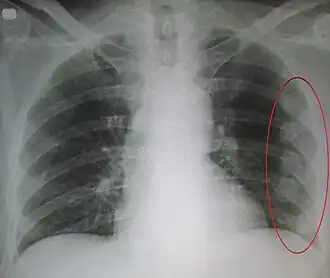

Fracture de côte sur un scanner thoracique Fracture de côte sur une radiographie standard

Fracture de côte sur une radiographie standard